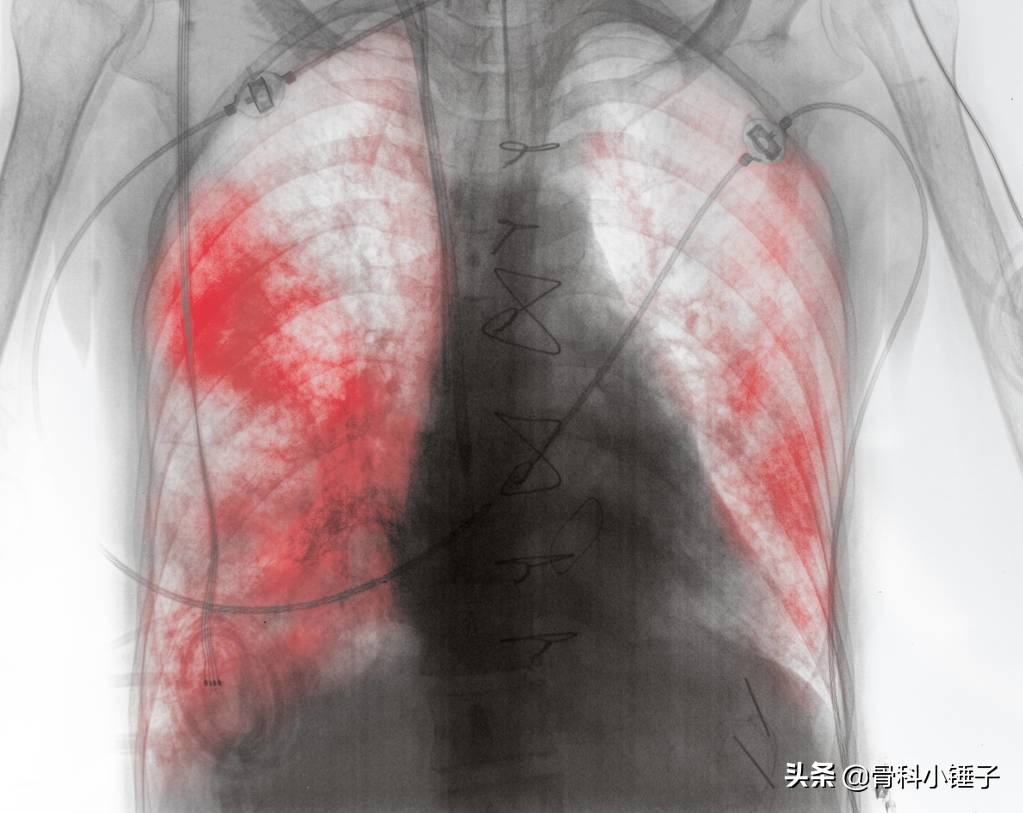

发病前局部皮肤先有灼痛,伴轻度发热、疲倦无力等全身症状。但也可以无前驱症状,经1~3天后,皮肤陆续出现散在红斑。继而在红斑上发生多数成簇的粟粒大至绿豆大小的丘疱疹,并迅速变为水疱。水疱壁紧张,光亮,疱水澄清,水疱表面大部有小凹陷。数日后疱液混浊化脓,破溃后形成糜烂面,最后干燥结痂,痂脱落后留下暂时性红斑。一般病程约2~4周。轻症患者只出现红斑及丘疹,不出现水疱,称为不全性带状疱疹。在恶性淋巴瘤、急性系统性红斑狼疮以及老年体弱者可出现坏疽性疱疹,愈后留下疤痕,称为坏疽性带状疱疹。带状疱疹可全身泛发,此时常伴有高热,并出现肺炎或脑炎,病情严重,如不及时抢救,可致死亡,称为泛发性带状疱疹。